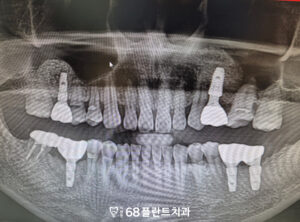

이렇게 환자분의 치아 상실 부위에는

임플란트를 식립하는 동시에,

부족한 뼈 높이를 보강하기 위해

상악동거상술을 함께 진행하였습니다.

이를 통해 임플란트가

안정적으로 자리 잡을 수 있는

튼튼한 기반을 마련할 수 있었으며,

장기적으로 저작 기능과 심미성을 회복하는 데

도움이 되도록 치료가 이루어졌습니다.

이렇게 철산역치과 이편한68플란트의

상악동거상술을 동반한 임플란트

사례를 소개해드렸는데요.